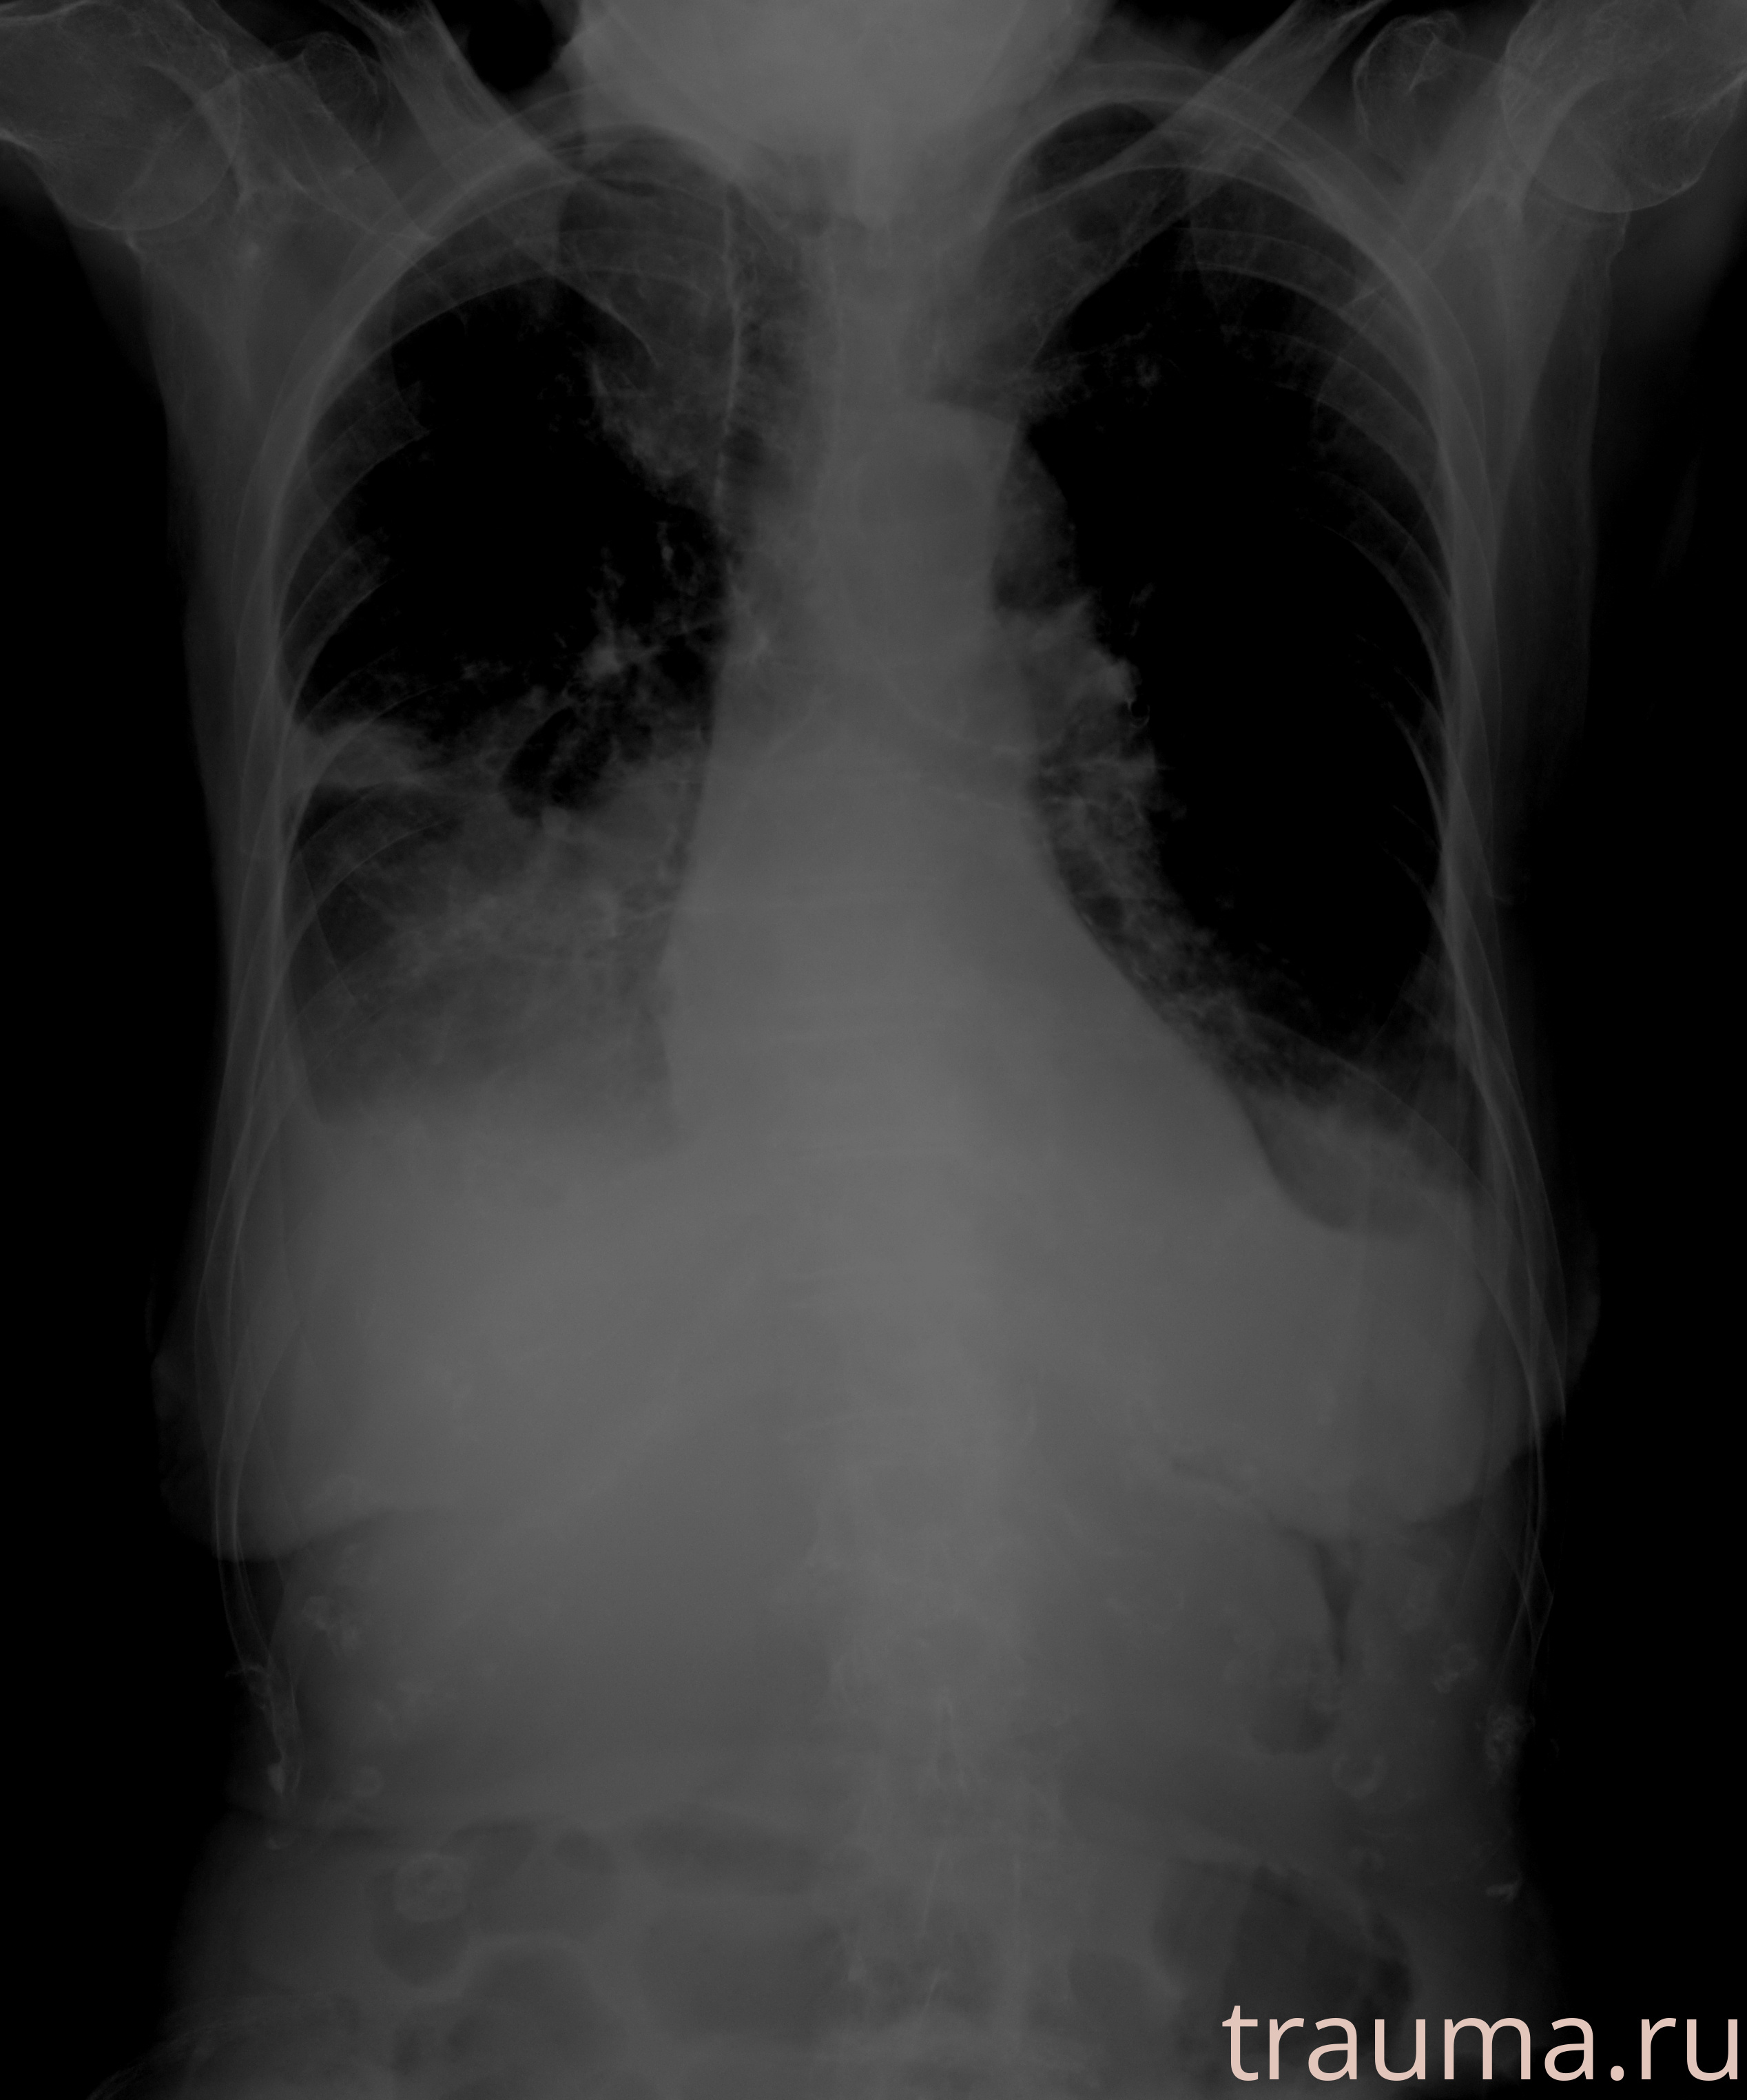

Рентгенограммы

Рентген на дому: по вашему адресу приезжает врач-рентгенолог, травматолог-ортопед с мобильным рентгеновским аппаратом, проводит диагностику травмы или заболевания, делает необходимые рентгенограммы, дает рекомендации по дальнейшему лечению. Получить качественные снимки в домашних условиях возможно благодаря уникальной методике, разработанной МосРентген Центром для института  Склифосовского

при переломе шейки бедра и пневмонии от компании МосРентген Центр - партнера Института имени Склифосовского